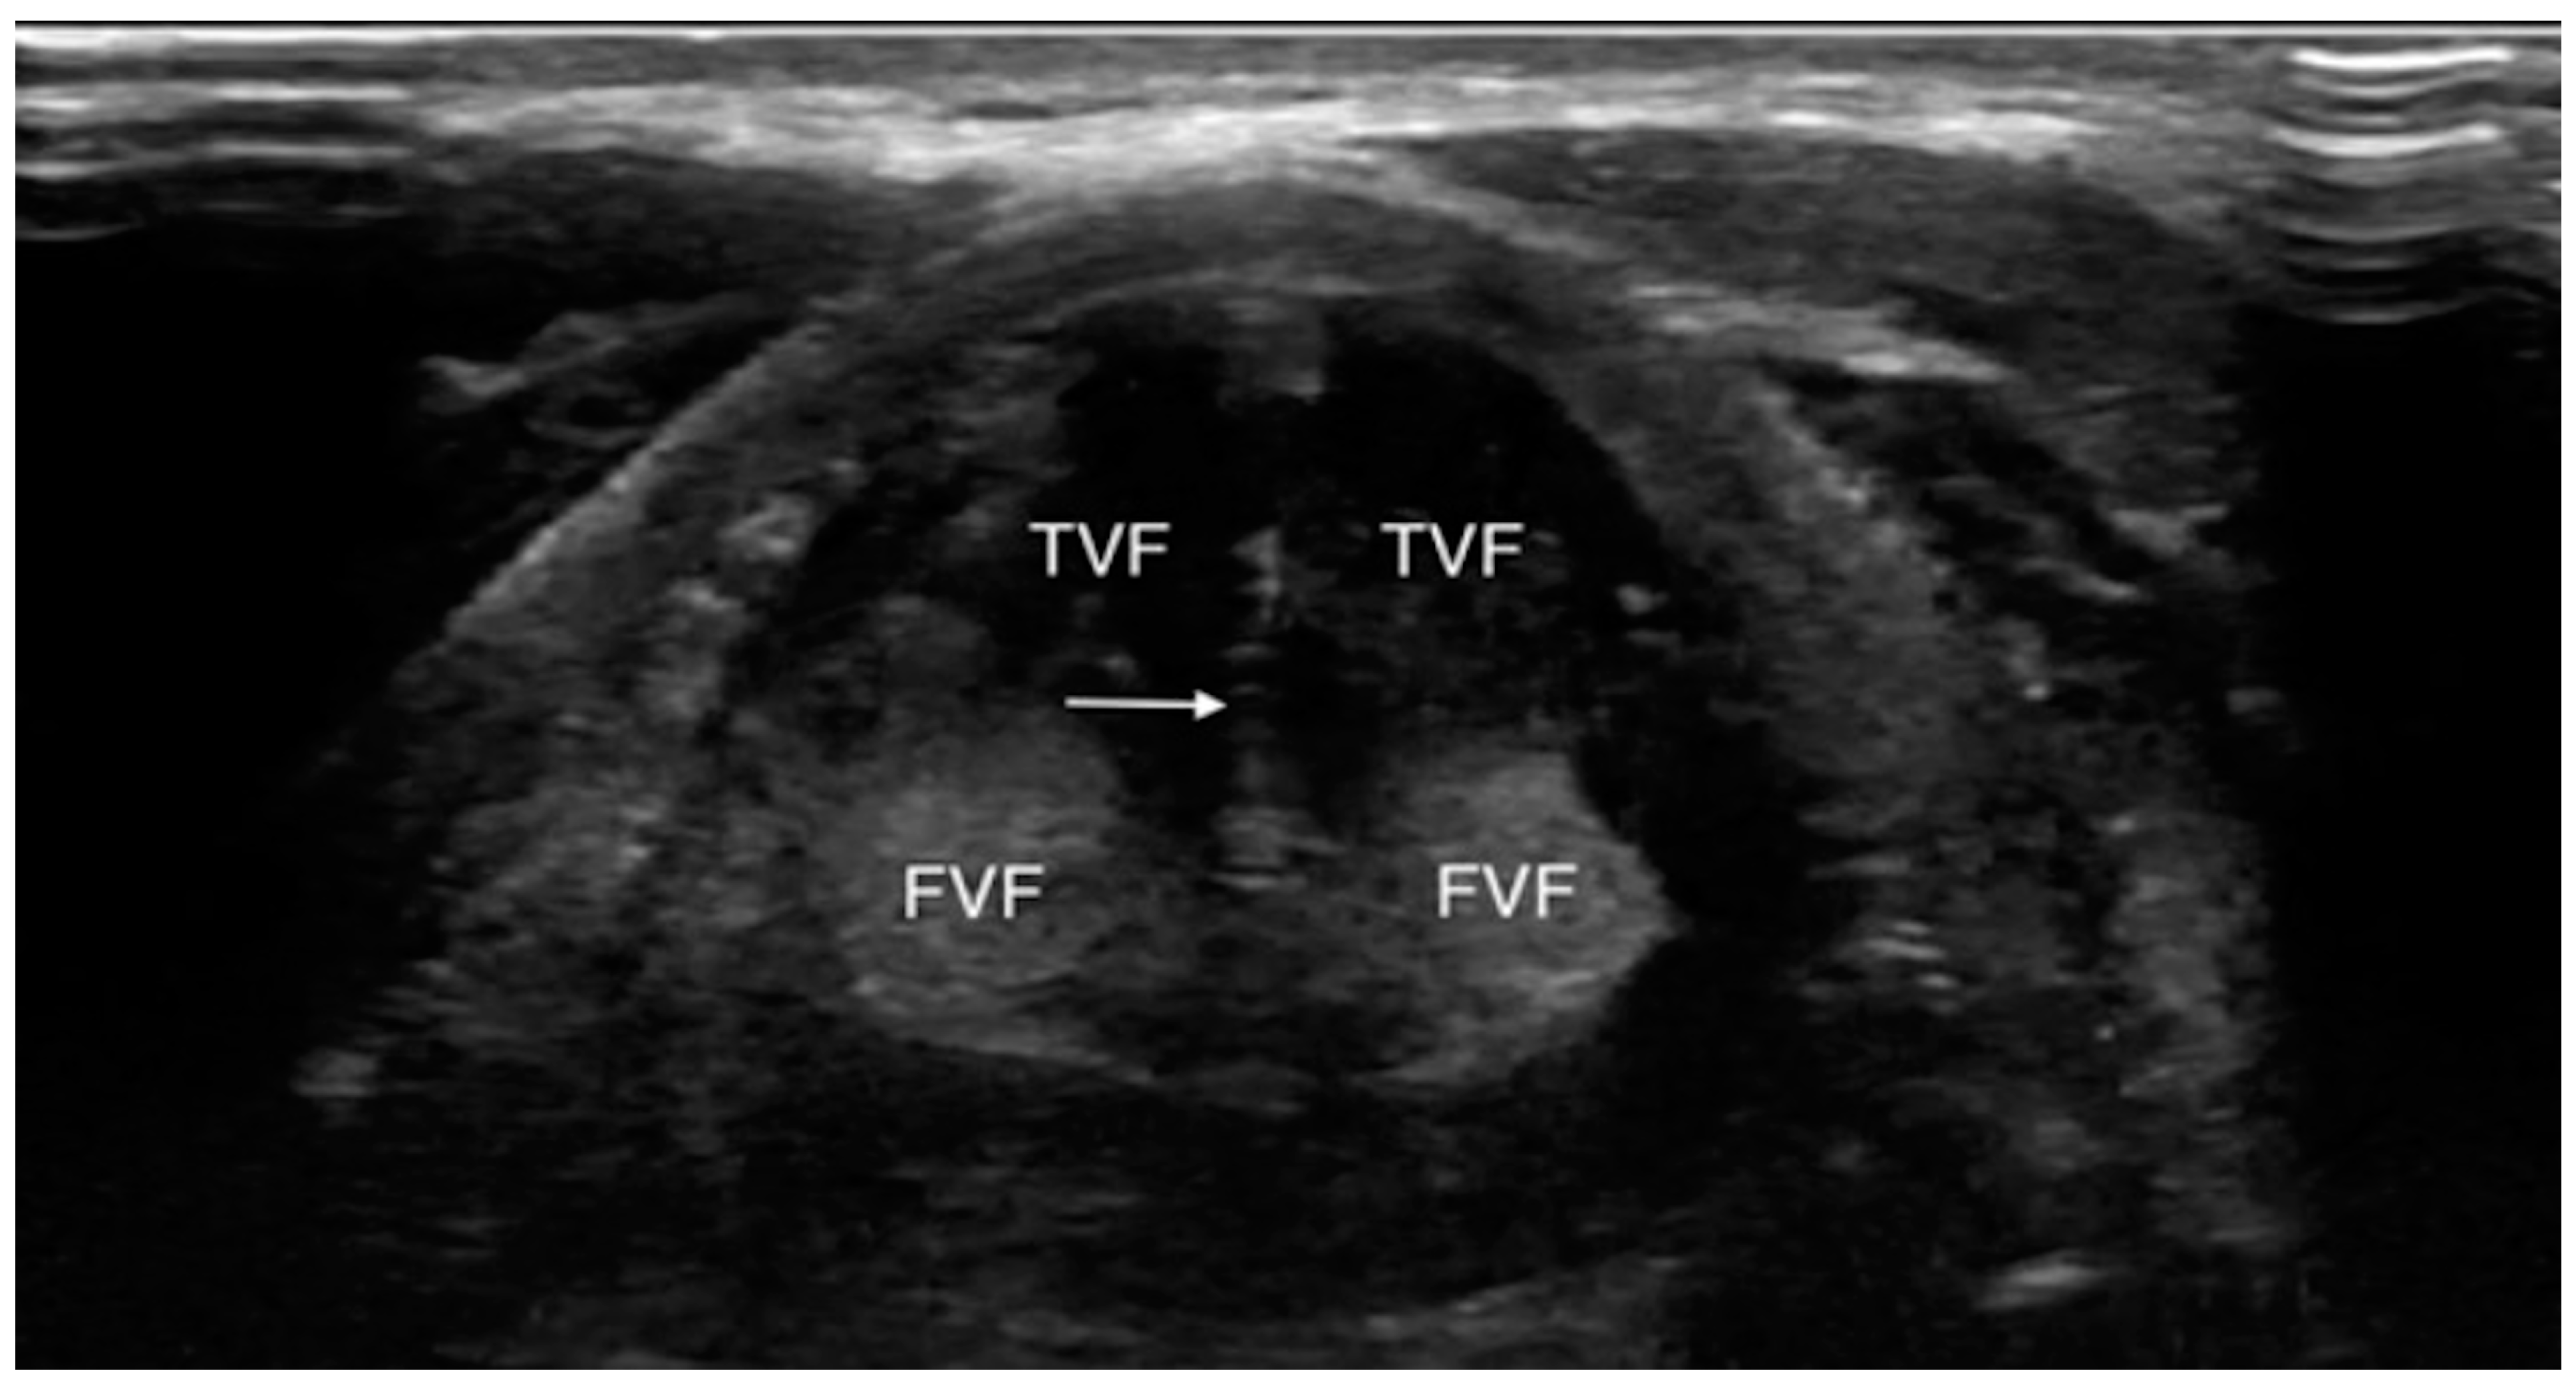

Even if the upper airway US is affected by some limitations due to the presence of artifacts interfering with ultrasound images and interpretation such as subcutaneous emphysema, posterior laryngeal injury, cartilage calcification and foreign bodies, its utilization has been reported in many clinical scenarios [20] (Figure 1 and Figure 2).

Figure 1.

Transverse view of normal vocal folds during valsalva (adduction). FVF, false vocal fold; TVF, true vocal fold. White arrow indicates hyperechoic medial margins of true vocal folds meeting in midline. Reproduced with permission of Dr. Noel from [20].